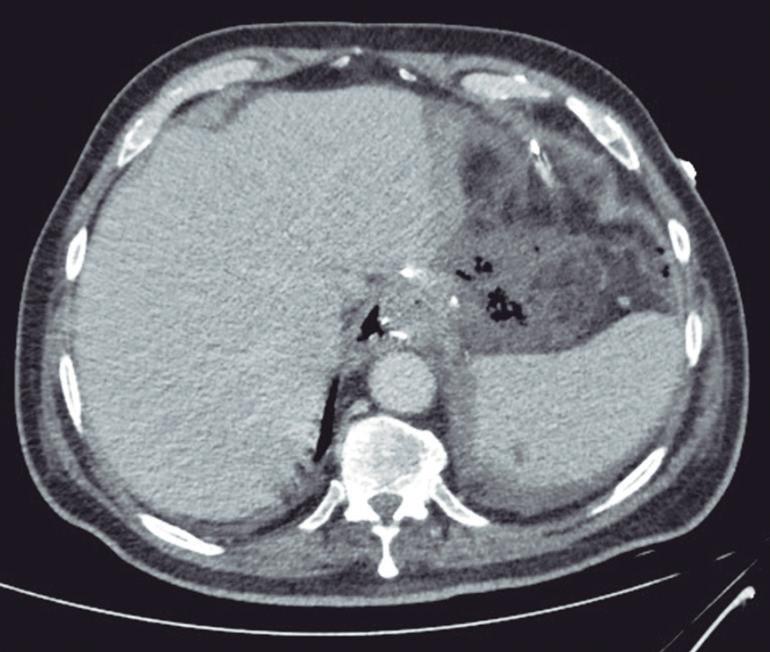

Evaluación endoscópica e histológica

La endoscopía superior es un procedimiento fundamental para el diagnóstico, la evaluación de la respuesta al tratamiento y el monitoreo a largo plazo de la actividad de la EEo. Los hallazgos endoscópicos típicos incluyen edema (reducción de vascularidad), anillos esofágicos fijos, exudados blancos, surcos longitudinales, estenosis, estrechamiento de la luz esofágica, friabilidad de la mucosa (mucosa en papel crepé) y una consistencia firme de la mucosa al realizar biopsias (signo de “tracción" o "resistencia”) en pacientes con fibrosis (Figura 1). Estos hallazgos no son patognomónicos y no constituyen un criterio diagnóstico; sin embargo, cuando se evalúa de forma cuidadosa, en la gran mayoría de los casos se pueden observar.19-21

En el panel A se observa un esófago con edema difuso y pliegues longitudinales; en el panel B se aprecia edema con pliegues y exudados blanquecinos; en el panel C se evidencia un estrechamiento luminal acompañado de anillos esofágicos y exudados; y en el panel D se muestra un desgarro mucoso posterior a la dilatación con bujía de Savary, hallazgo esperado tras este procedimiento terapéutico.

Figura 1. Características endoscópicas de la esofagitis eosinofílica